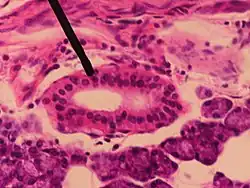

Section of submaxillary gland of kitten. Duct semidiagrammatic. X 200. -

Section of portion of mamma.